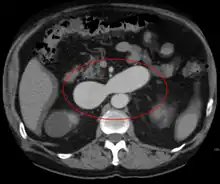

AVMs are diagnosed primarily by the following imaging methods:

- Computerized tomography (CT) scan is a noninvasive X-ray to view the anatomical structures within the brain to detect blood in or around the brain. A newer technology called CT angiography involves the injection of contrast into the blood stream to view the arteries of the brain. This type of test provides the best pictures of blood vessels through angiography and soft tissues through CT.

- Magnetic resonance imaging (MRI) scan is a noninvasive test, which uses a magnetic field and radio-frequency waves to give a detailed view of the soft tissues of the brain.

- Magnetic resonance angiography (MRA) – scans created using magnetic resonance imaging to specifically image the blood vessels and structures of the brain. A magnetic resonance angiogram can be an invasive procedure, involving the introduction of contrast dyes (e.g., gadolinium MR contrast agents) into the vasculature of a patient using a catheter inserted into an artery and passed through the blood vessels to the brain. Once the catheter is in place, the contrast dye is injected into the bloodstream and the MR images are taken. Additionally or alternatively, flow-dependent or other contrast-free magnetic resonance imaging techniques can be used to determine the location and other properties of the vasculature.